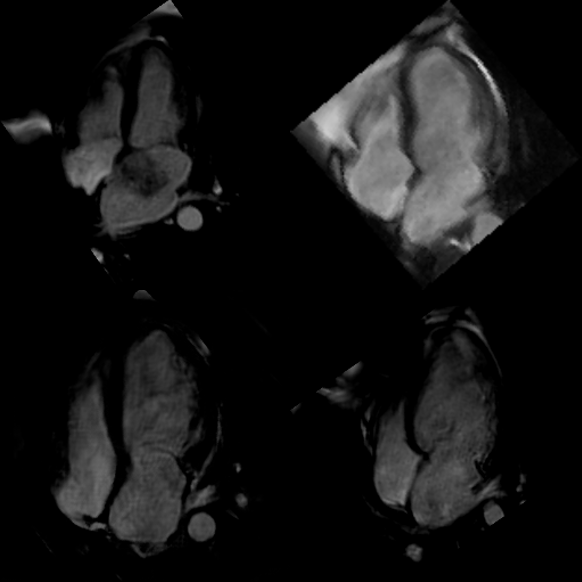

Refer to caption ABCD

Figure 9: A sample from the confusion test containing four randomly selected, generated, or original MRI images. Cardiologists were asked to identify the generated ones.444Labels: A&B, original; C&D, synthesized.

The first question we asked cardiologists was to identify which of the shown views are synthetic. We call this first evaluation test the ”Confusion Test”. As its name implies, we aimed to assess how well a trained expert’s eye can distinguish the transformed (synthetic) cardiac MRI frame from the original counterpart. Each cardiologist were shown 200 cardiac MRI views, consisting of 100 synthetic and 100 original cardiac MRI images, and were tasked with identifying the synthetic ones. Frames are shown to the expert randomly, ensuring that each frame has a probability of 0,5 to be an original or generated view. Therefore, if the quality of the transformed cardiac MRI views matches their actual counterparts, one can expect an average accuracy of 0.50.50.50.5 or lower, otherwise, the accuracy can be expected to be higher than 0.50.50.50.5. Other standard evaluation metrics such as Precision, Recall, Specificity, F1 score, false positive rate (FPR), and Matthews correlation coefficient (MCC) are also computed for an overall quantitative evaluation. Figure 4 shows a sample from the Confusion Test555More examples are available in Appendix B.. We retrieved each assessment from the four cardiologists and presented results in a confusion matrix (CM).

Figure 34: Four samples from the confusion test, consisting of randomly selected synthetic and original cardiac MRI images. Cardiologists were asked to differentiate between the synthetic and original images. The samples include: A (original), B (original), C (synthetic), and D (synthetic).